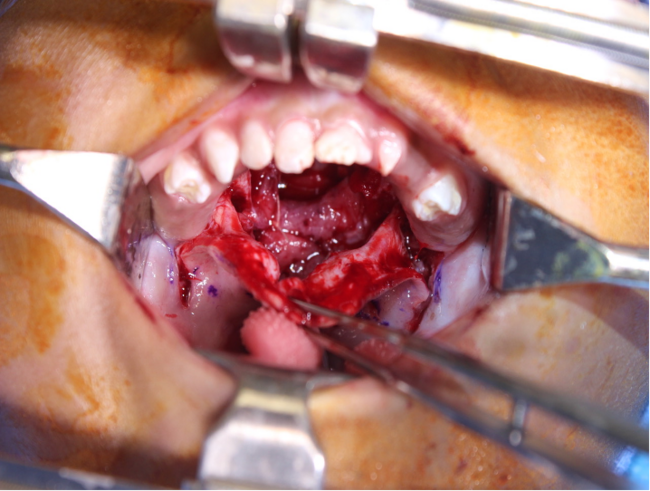

At the age of 19 months, the decision was made to proceed with palate repair. The preoperative plan was to perform a Furlow palatoplasty with bilateral relaxing incisions and vomerine flaps for closure of the anterior palatal defect. Consent was also obtained for bilateral buccal flaps, should they be necessary. Closure of the soft palate nasal mucosal, muscular, and oral mucosal layers was achieved through Furlow palatoplasty with bilateral von Langenbeck–type relaxing incisions. Closure of the hard palate proved more difficult. The nasal layer was closed with bilateral vomerine flaps as planned; however, closure of the oral layer with the available tissue was a challenge, and a bipedicled anterior palatal flap was employed (Figure 2B-D). In short-term follow-up, this patient has done well and has been decannulated. The lateral areas of the anterior palate were well mucosalized at 3 weeks following surgery. He is active in speech therapy and progressing as expected. He has shown no signs of maxillary growth restriction as of 9 months following surgery.